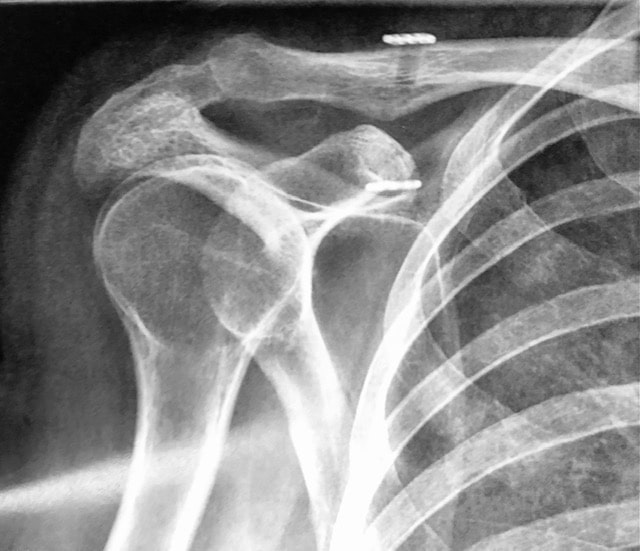

Une radiographie permet d’établir le diagnostic et, après la réduction, d’en contrôler l’efficacité. Après réduction la douleur cesse. Une immobilisation est préconisée, coude au corps ou en position neutre.

Le traitement préconisé en cas de luxation, subluxation et instabilité, est la rééducation. Elle permet d’améliorer la stabilité et de supprimer la douleur. Si malgré la rééducation les luxations deviennent récidivantes, les subluxations trop gênantes et l’épaule instable, trop douloureuse ou invalidante, limitant les activités et gênant la qualité de vie, un bilan s’impose et une chirurgie peut être proposée. Un bilan radiographique complété d’un scanner, ou d’une IRM, et couplé à une injection de produit de contraste permet d’identifier les lésions de l’os (glène ou tête humérale) et de mettre en évidence une fissure du bourrelet, ou un arrachement des ligaments.Un bilan radiographique complété d’un scanner ou d’une IRM et couplé à une injection de produit de contraste permet d’identifier les lésions de l’os (glène ou tête humérale) et de mettre en évidence une fissure du bourrelet, ou un arrachement des ligaments.